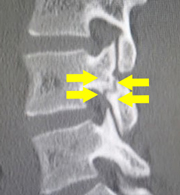

せぼね(脊椎)は7個の頚椎、12個の胸椎、5個の腰椎と仙椎から構成されます。腰椎は主に5つの骨と、間にあるクッションのような椎間板、また神経組織が通っている脊柱管から成り立っています。腰椎分離症とは、腰の骨の後ろの部分にある上・下関節突起間部と呼ばれる部分の連続性が断たれた状態を言います。上・下関節突起間部に疲労骨折が生じ、偽関節(骨がくっつかない)になると腰椎分離症となります。さらに、腰の骨が前方にすべってしまうと腰椎分離すべり症と呼ばれ、分離症患者の10~20%が分離すべり症に移行すると言われています。

せぼねの変形や椎間板の傷み具合、すべりや不安定性の有無、脊柱管の狭さ、またせぼね全体のバランスなどを見るためにX線検査やCT検査、MRI検査などを行います。進行例では脊柱管の狭さをより詳しく評価するために入院して脊髄造影検査や、同時にどの神経が痛みの原因となっているかを明らかにするために神経の枝に直接麻酔薬を注入する選択的神経根ブロックを行う場合があります。成人期では血管性の下肢の痛みがないか評価するために両手足の血圧を測ったり、骨粗鬆症の有無を評価するために骨密度検査を行うこともあります。